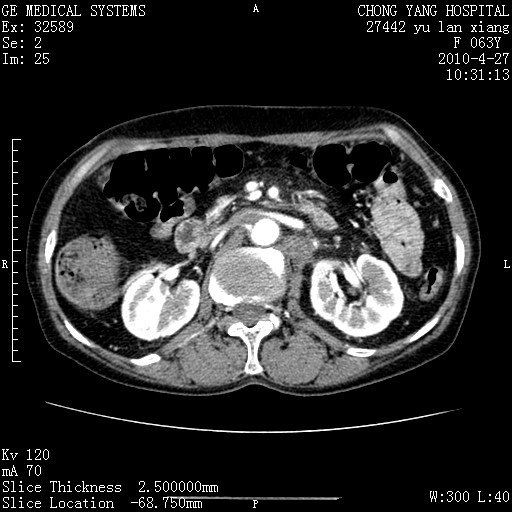

标题: CT26066:F63Y 上腹正中压痛半月,CA199:7400u/ml,MR示胰腺炎伴 [打印本页]

胰腺癌侵犯腹腔动脉干-分支、胃壁、左侧膈肌伴胰周及腹膜后淋巴结转移、胆囊切除术后。

胰腺癌侵犯腹腔动脉干-分支、胃壁、左侧膈肌伴胰周及腹膜后淋巴结转移、胆囊未显影。